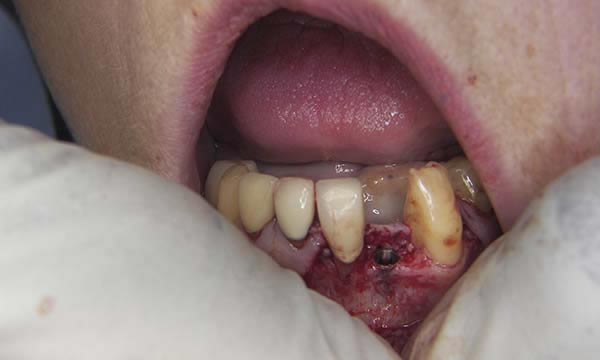

Case B

This gentleman had lost his heavily restored UL4 and decided to close the space with an implant retained crown. The thin buck-palatal width required careful placement to avoid fenestration bucally. A tooth bourn position guide was used to place the implant predictably and within the aesthetic envelope. The implant was restored after three months of osseointegration with a bonded crown.

During Treatment